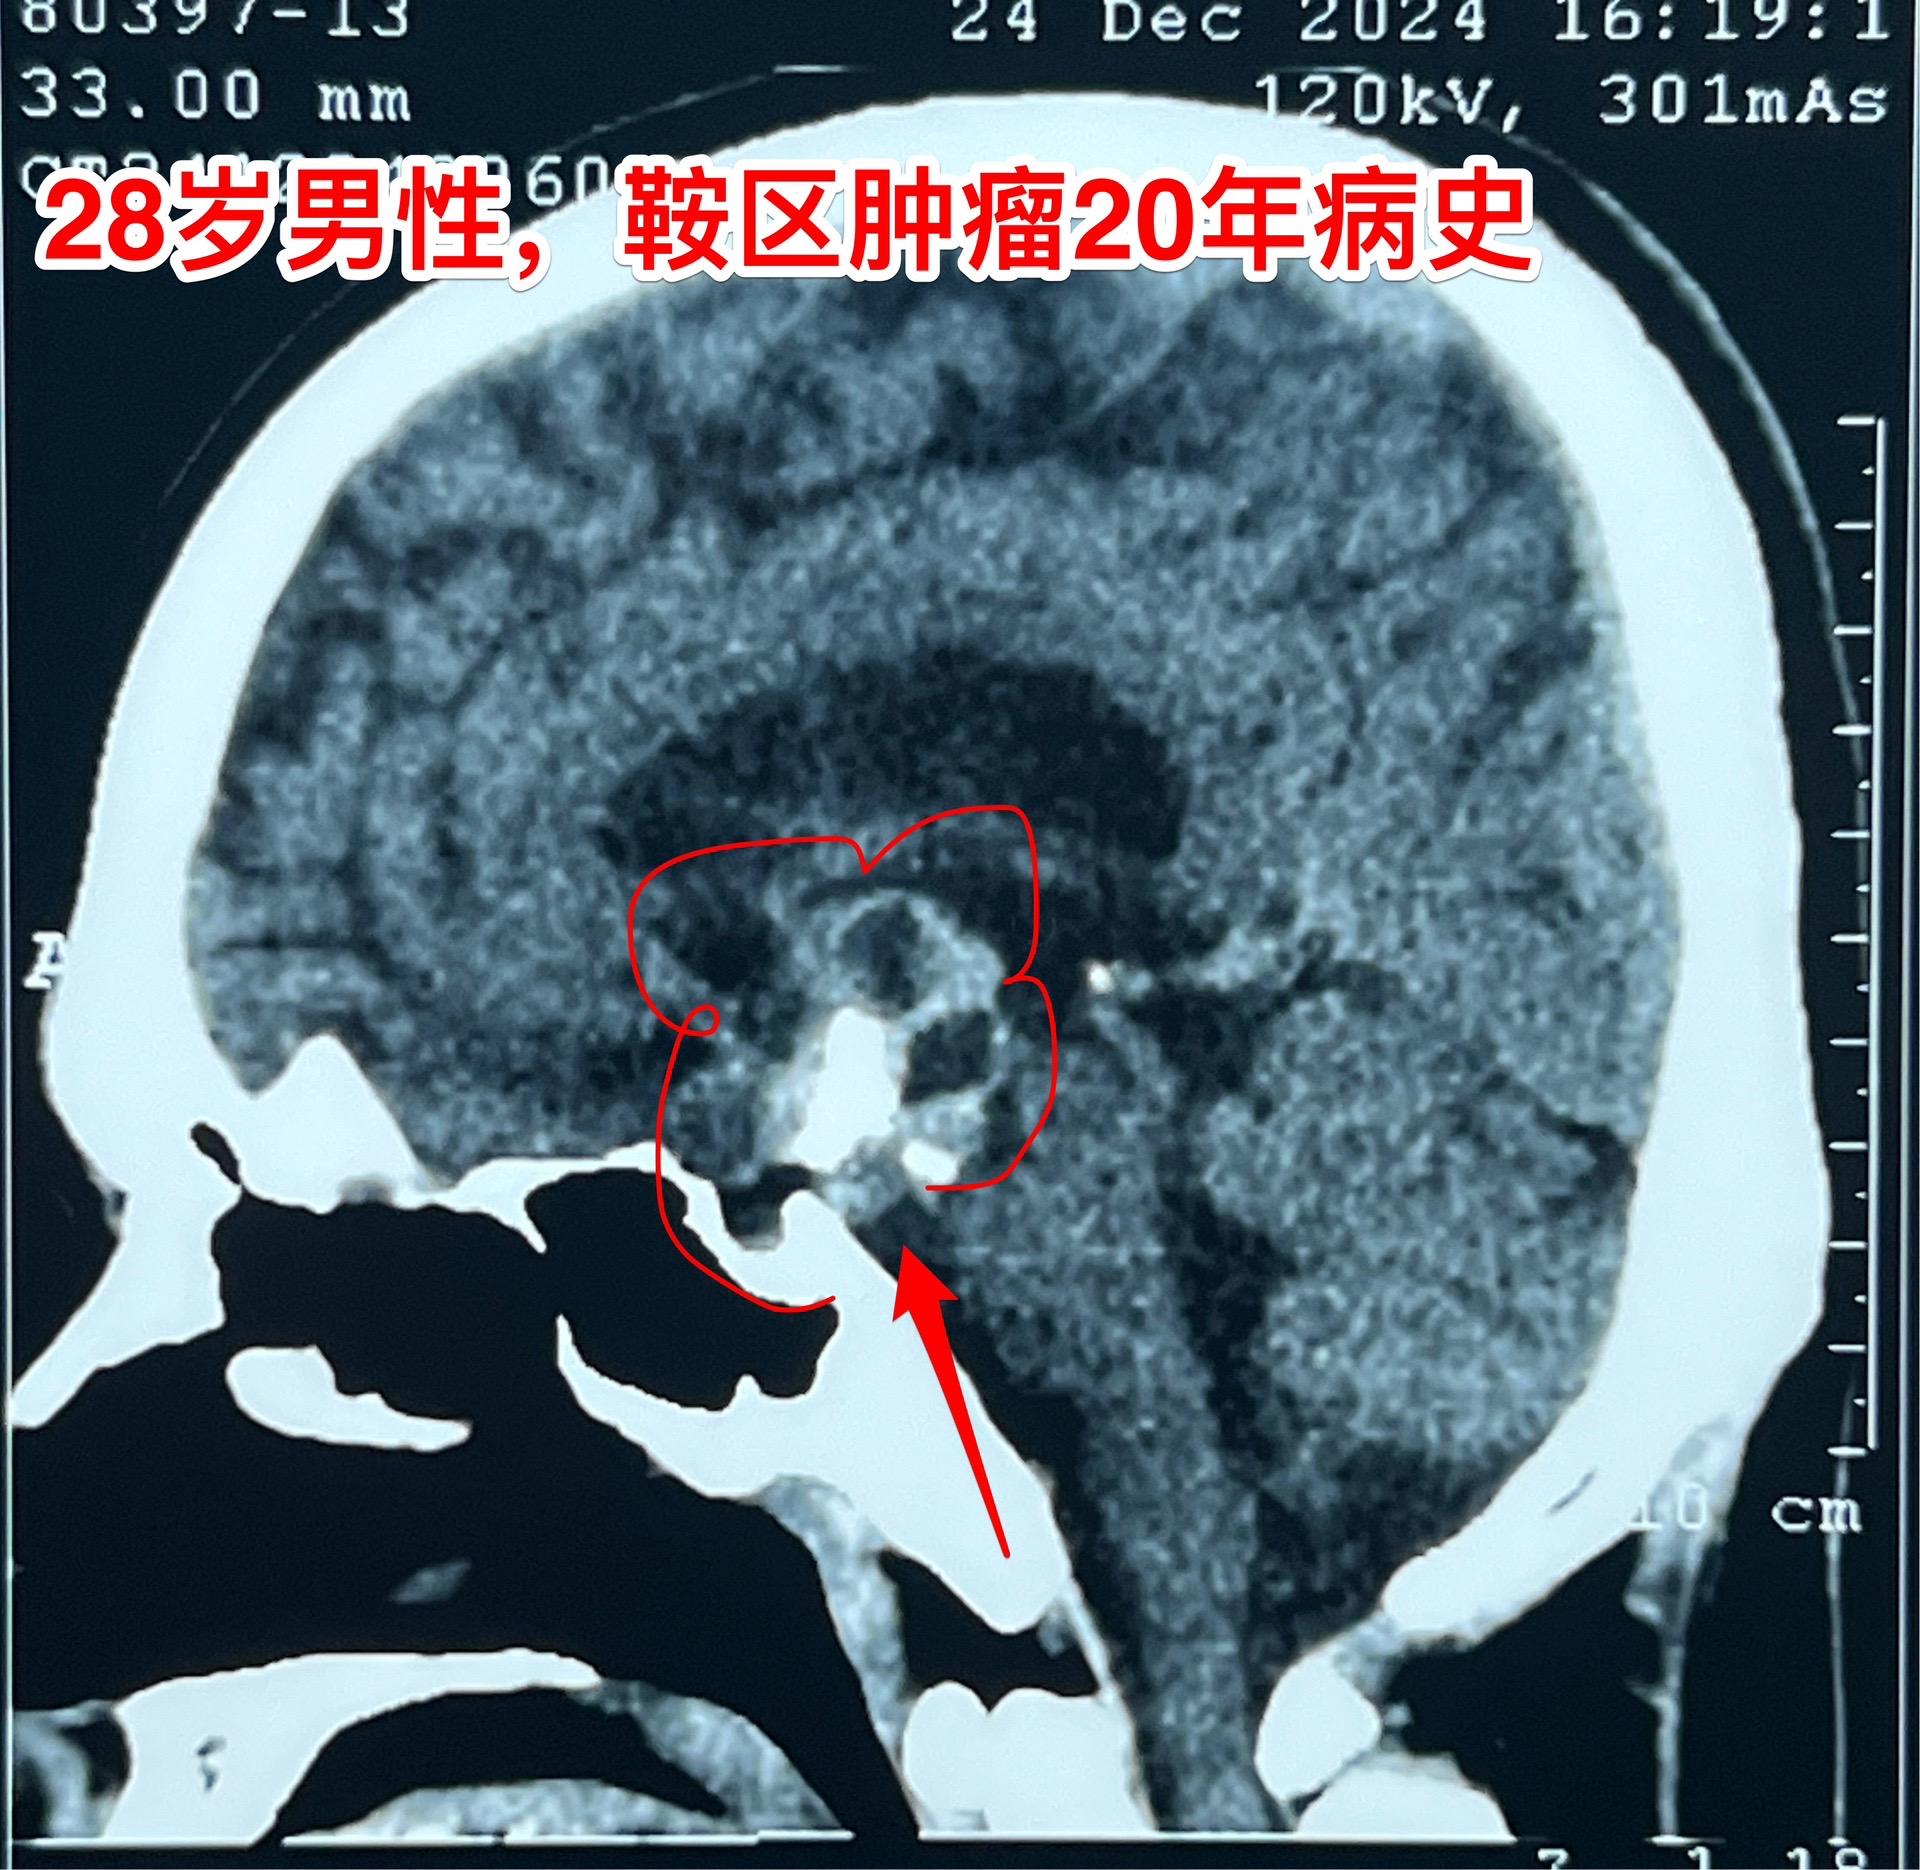

鞍区肿瘤长了20年,才下决心作手术!元旦之后的第一个鞍区肿瘤手术,怀疑是颅咽管瘤。 患者为28岁男性,20年前就发现脑部长了肿瘤,当时患者才八岁,三博脑科医院刚刚成立不久,他们就到三博脑科医院就医。因故未作手术,密切观察。 患者随后能正常读书,生长发育也还不错。后来还考上了大学,毕业后曾经在上海工作过。多次复查磁共振显示鞍区肿瘤体积在增大。而且患者也感觉视力方面出现了问题,在多个著名的医院就医过,最后下决心来找我作手术。 一月三日手术中发现肿瘤中心有钙